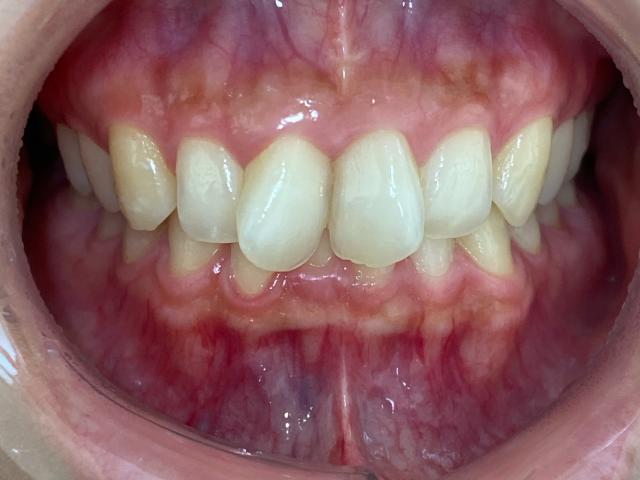

拝見したところ、上左右の前歯(中切歯/1番)はスペース不足のため歯が捻れて生える「捻転」が見られました。

また、上左右の前歯は横から見た時に少し前に出ている「上顎前突(出っ歯)」の状態でもありました。

下の前歯4本(中切歯、側切歯/2番)は、デコボコに並ぶ「叢生(そうせい)」がやや認められました。